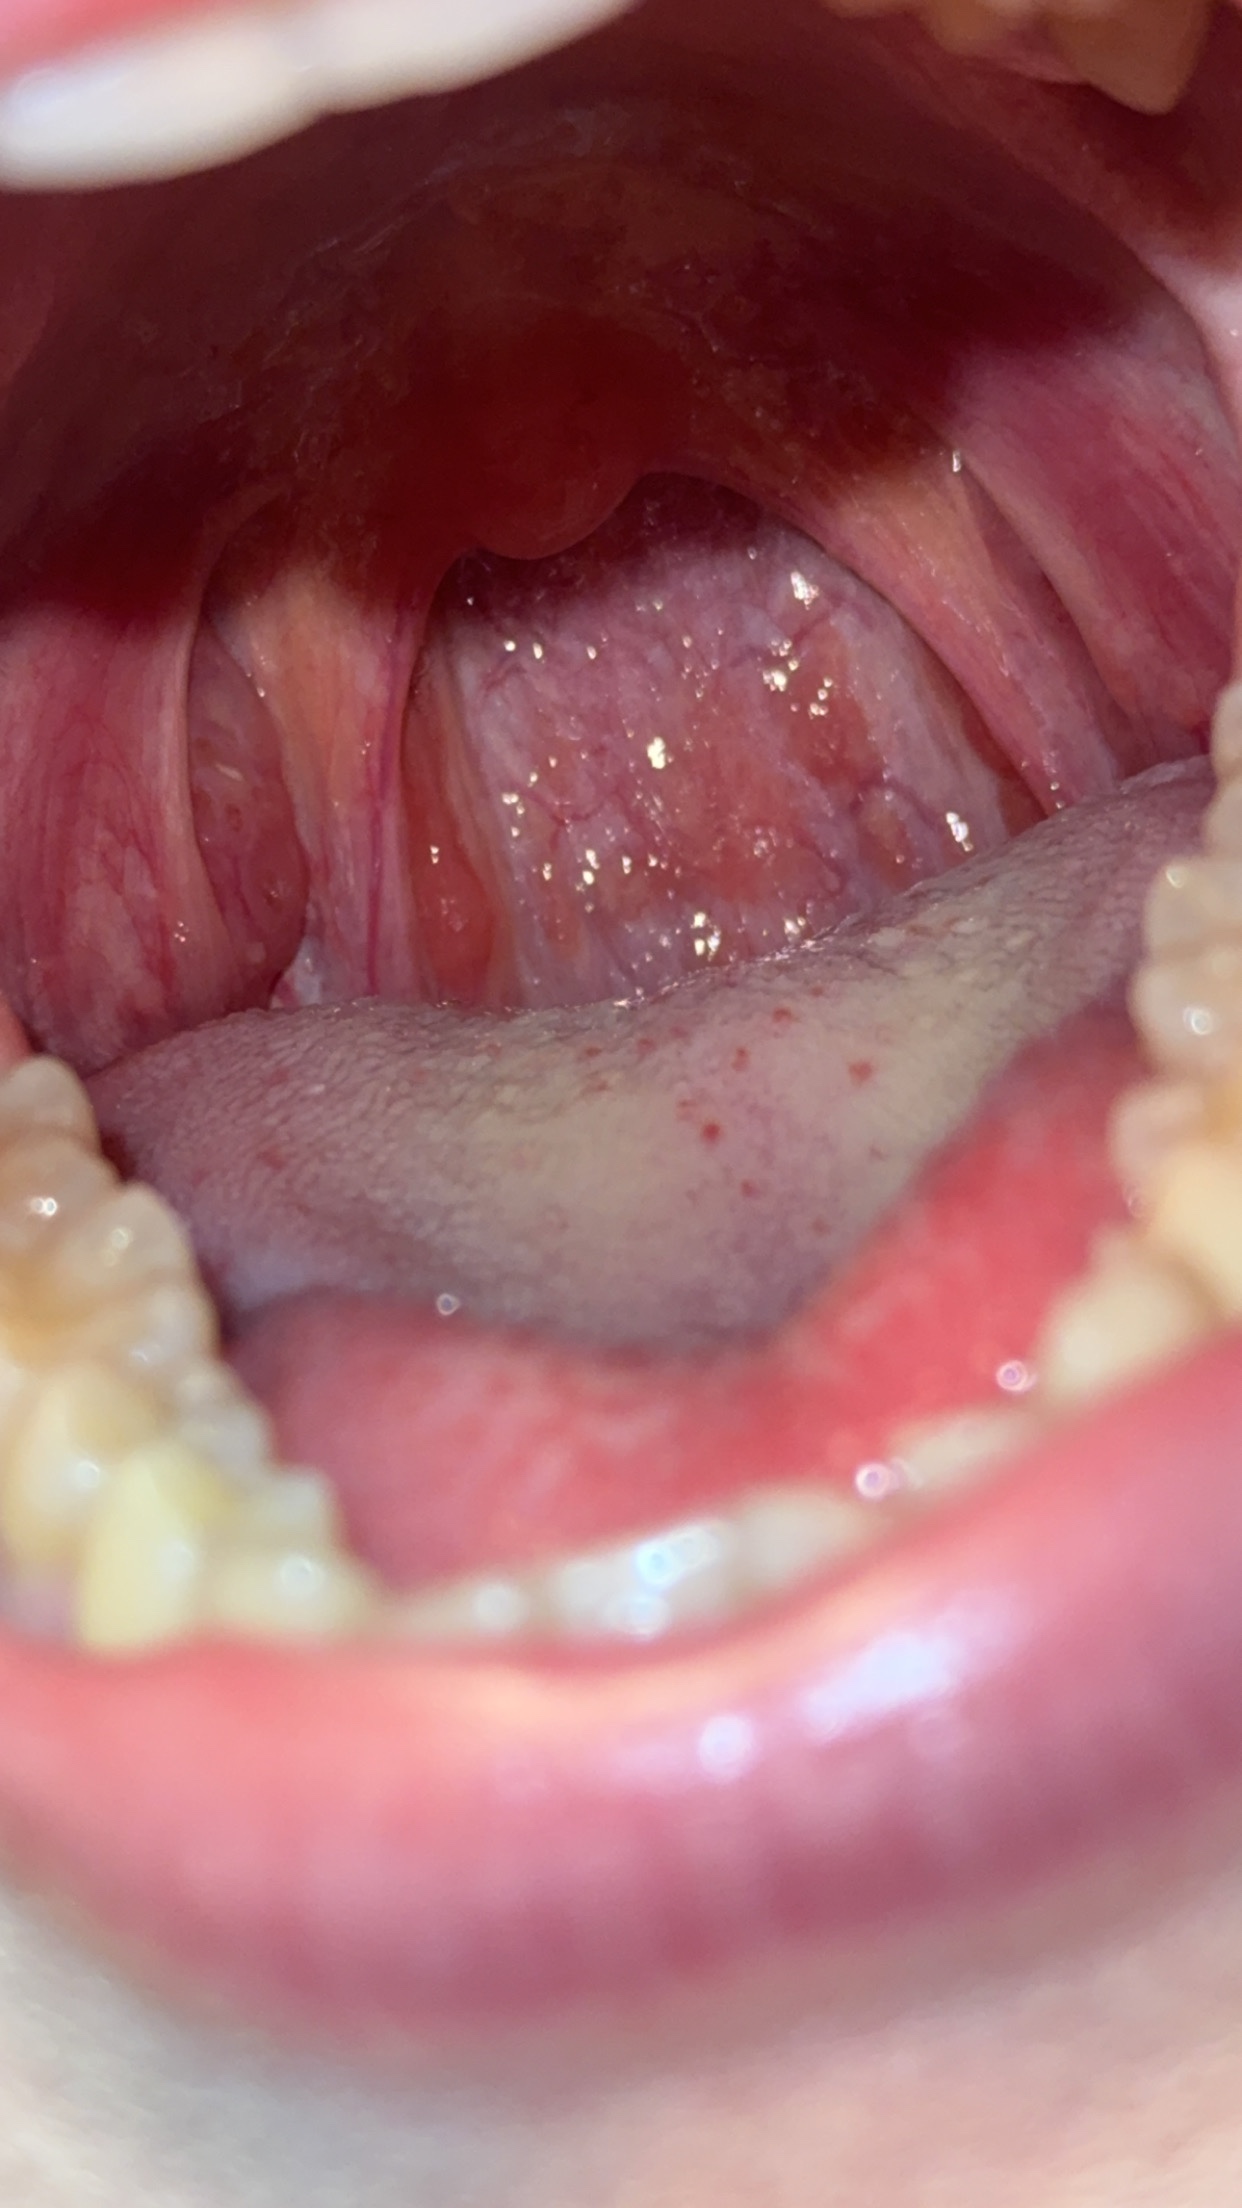

Здравствуйте, красное горло. Фото ниже.

Есть ощущения кома в горле, бывает иногда трудно глотать (делаю насильно, дабы проглотить сопли). У меня есть насморк. Ходила к Лору, смотрели, брали анализы - все чисто. Я полагаю, что это постназальный затек или фарингит, однако никто не подтвердил диагноз, хотя это состояние вызывает дискомфорт. Жкт в норме. Других проблем нет.